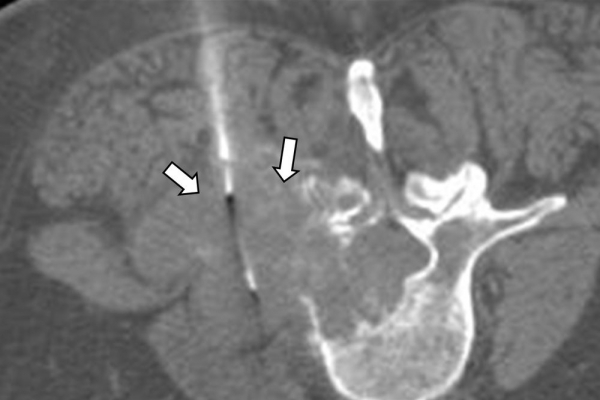

Η διαδερμική βιοψία είναι μία ελάχιστα επεμβατική μέθοδος λήψης υλικού από τον όγκο για κυτταρολογική και ιστολογική εξέταση, από εστιακές αλλοιώσεις του ήπατος, πνεύμονα, νεφρού κλπ. Συστήνεται από τον κλινικό ιατρό ανάλογα με το είδος και το μέγεθος της βλάβης και πραγματοποιείται με ασφάλεια από επεμβατικό ακτινολόγο με την καθοδήγηση αξονικού τομογράφου ή υπερήχων. Στη σύγχρονη ογκολογική θεραπεία όπου γίνεται προσπάθεια καταπολέμησης του καρκίνου σε μοριακό επίπεδο κρίνεται αναγκαία η ακριβής ιστολογική ταυτοποίηση του όγκου ώστε να εφαρμοσθεί εξατομικευμένη θεραπεία για το βέλτιστο αποτέλεσμα. Οι κατευθυνόμενες βιοψίες στοχευουν στο να παρέχουν στον κλινικό ογκολόγο το απαραίτο ιστοπαθολογικό υλικό που θα του επιτρέψει να εφαρμόσει την κατάλληλη θεραπεία για τον ογκολογικό ασθενή.